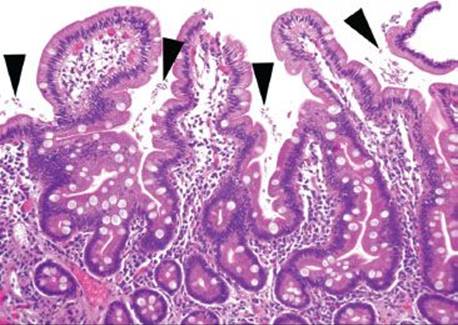

Figure 3.316 Isosporiasis. This intermediate power view shows how easy it is to miss Isospora. At low power, only gastric foveolar metaplasia and perhaps a slight increase in lamina propria eosinophils is seen. Other fields of this same case were essentially normal, emphasizing that every biopsy needs a few high power fields of attention for such extremely subtle diagnoses.

Figure 3.317 Isosporiasis. On higher power, a slight prominence of lamina propria eosinophils serves as a red flag to the diagnosis. Arrowheads highlight the Isospora organisms, which are obligate intracellular parasites and are found in the paranuclear or subnuclear cytoplasm.

Isosporiasis is among the more common protozoan causes of severe diarrhea in AIDS patients (Figs. 3.316–3.318).190 The Isospora belli organisms are spread via contaminated water or fecal–oral contamination. They localize to the small bowel surface and are exceedingly easy to miss owing to sometimes unremarkable background mucosa and sparsely distributed organisms (Figs. 3.316–3.321). Diagnostic confirmation is facilitated through identification of the oocysts in stool samples or duodenal aspirates.191 Standard therapy consists of trimethoprim–sulfamethoxazole, which is often long term in severely immunocompromised patients.